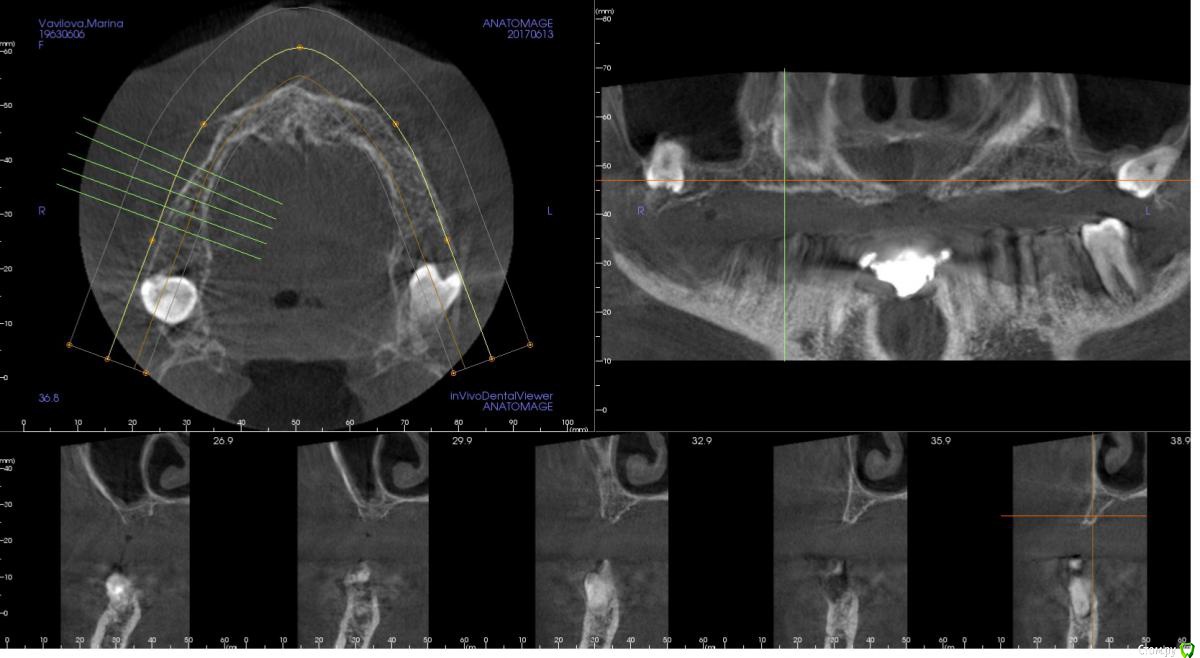

kamranchick Опубликовано 2 ноября, 2017 Поделиться Опубликовано 2 ноября, 2017 (изменено) Планируется установка 3 имплантатов в 1 сегменте, и будет балочная конструкция.хочется пойти двухэтапным протоколом. так как гигиена и вредные привычки меня отпугивают.Какой вариант тут будет предпочтительным Изменено 2 ноября, 2017 пользователем kamranchick Ссылка на комментарий

kamranchick Опубликовано 2 ноября, 2017 Автор Поделиться Опубликовано 2 ноября, 2017 А сколько всего планируется имплантов? А если только во фронте 4 поставить?6 имплантатов, 3 с одной поставил, теперь 3 с другой, во фронте кости кот наплакал( Ссылка на комментарий

kamranchick Опубликовано 2 ноября, 2017 Автор Поделиться Опубликовано 2 ноября, 2017 Гигиена просто катастрофа.Балка чтобы конструкция была условно сьеигаячСинусы планирую тоже сделать.А насчёт зигом ну это слишком)))) Ссылка на комментарий

zzkz Опубликовано 3 ноября, 2017 Поделиться Опубликовано 3 ноября, 2017 согласен за синус и отсроченную нагрузку через 6 мес Ссылка на комментарий